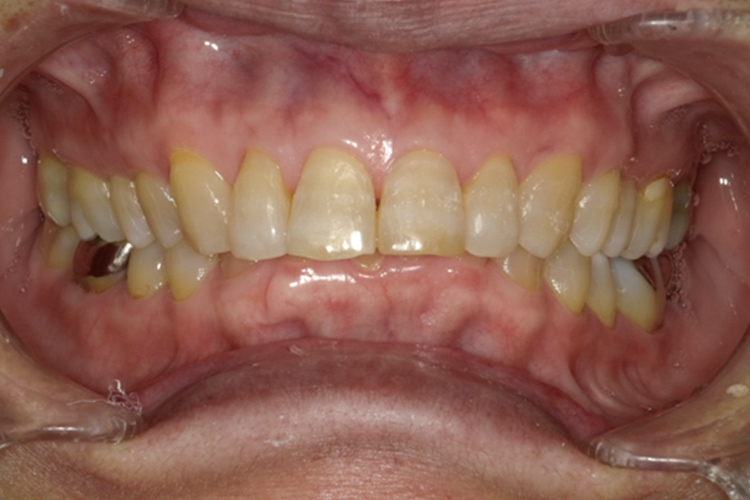

治療前

治療後